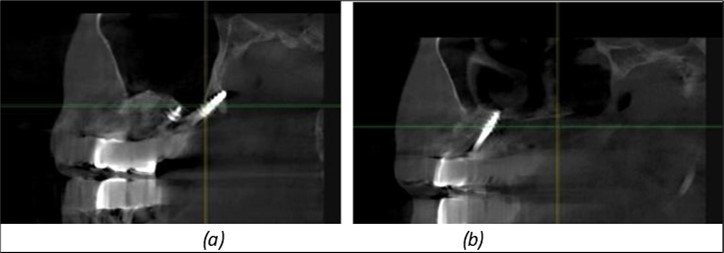

June 2022: Patient presented to our clinic for immediate-loading implant treatment At the time of presentation in 06. 2022, radiologically, advanced peri- implantitis is observed around the implants, with loss of native bone in the affected distal areas (Figure 1)

Figure 1.Panoramic overview picture before rehabilitation 06.2022

Figure 3.Panoramic pictures after removal of implants affected by peri-implantitis, extractions, alveolar crest regularization, and insertion of corticobasal and TPG implants (07.2022)